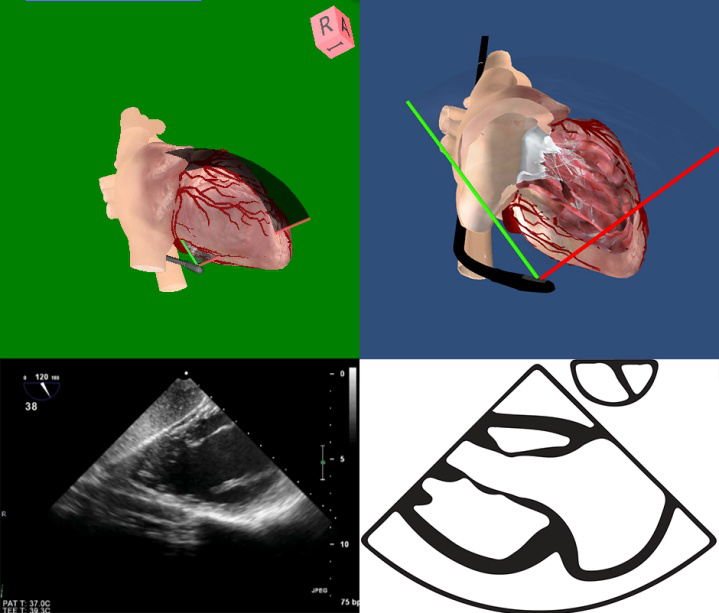

图2 2D和3D图像及成像原理 图3食管中段4腔心切面及模型图

2D或是3D图像(图2)都需要定义视角,采取面对心脏模型的视角,有2个理由:①面对心脏模型与系统解剖学方位一致,便于沟通;②面对心脏模型有利于实现从TEE到TTE的快速切换。以食管中段4腔心切面为例,描述探头与图像的位置关系理解图像和心脏模型的位置关系(图3),直观地显示了探头、切面与心脏模型的空间关系。

四腔心 (ME 4 chambers) TEE-Focus基本切面

0°~20° |

|

左、右心房位于近场,二、三尖瓣位于中场,左右心室位于中、远场。

常不能显示心尖,左右心室之间为前室间沟。显示二尖瓣前外乳头肌。

可观察4个心腔的比例。 |

4.食管中段四腔心切面(图5-4) ①各房室大小及其比例;②切面中心室壁的厚度、搏动幅度、连续性;③二尖瓣和三尖瓣的形态结构和开闭功能;④腔内血流是否正常。